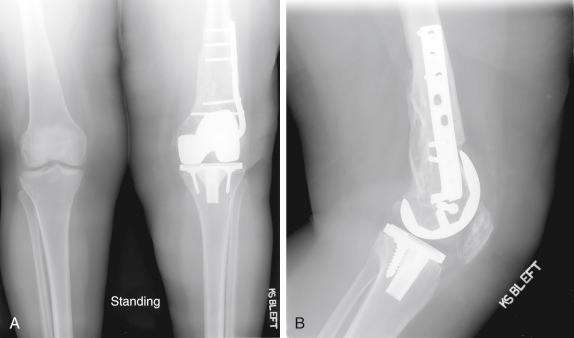

Radiographs demonstrated a cemented cruciate-retaining TKA with evidence of asymmetric polyethylene wear and prior internal fixation of a supracondylar femur fracture with a blade plate ( Fig. 36.2 ). The clinical workup was negative for infection.

FIGURE 36.2, Anteroposterior ( A ) and lateral ( B ) radiographs of the left knee demonstrate a cemented cruciate-retaining total knee arthroplasty with medial polyethylene wear and evidence of prior internal fixation of a supracondylar distal femur fracture with a blade plate.